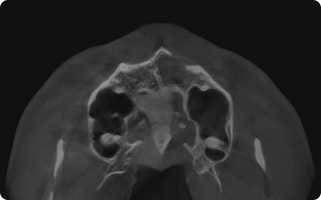

구강 검진, 촉진, 교합 검사 또는 파노라마, CBCT, MRI 촬영을 통해

눈에 보이지 않는 부위까지 선명하게 관절 및 디스크 상태를 확인합니다.

정밀 진단

- 구강 검진, 촉진, 교합 검사

- 필요 시 파노라마, CBCT, MRI 촬영을 통해 관절 및 디스크 상태 확인